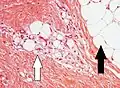

Lipoblasts (white arrow) and lipocytes (black arrow), in a case of lipoblastoma -

Lipid-laden histiocytes may mimic lipoblasts, but have lightly eosinophilic cytoplasm and a small normochromatic nuclei which are not hollowed out from the lipid vacuoles.[6]

Lipoblasts are seen in liposarcoma[7] and characteristically have abundant multivacuolated clear cytoplasm and a dark staining (hyperchromatic), indented nucleus.